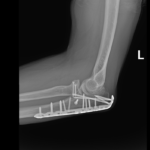

if the fracture is displaced, surgery may be needed to put the bone back into the correct position and fix the bone with Plates & screws or nails for adequate healing to occur.

- Elbow Fractures.